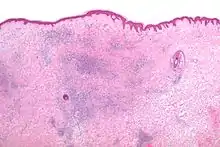

تتسبب لسعات الحشرة الغير سامة لمعظم الناس، حكة مزعجة شديدة (الشرى الحطاطي) . قد تظهر القرصة كبقعة صغيرة مرتفعة حمراء ؛ و قد تسبب حويصلة فقاعية. للأسف الرغبة في الهرش عادة ينتج عنها قرحة مفتوحة قد تصبح ملوثة و تأخذ مدة أطول للالتئام. في بعض أجزاء من العالم، تكون لسعات الحشرة مسببة لمشاكل أكثر، حيث تكون الحشرات ناقلة أو عامل وسيط للأمراض مثل الملاريا ، مرض لايم ، مرض الريكتسيا و حمى الضنك (أبو الركب).